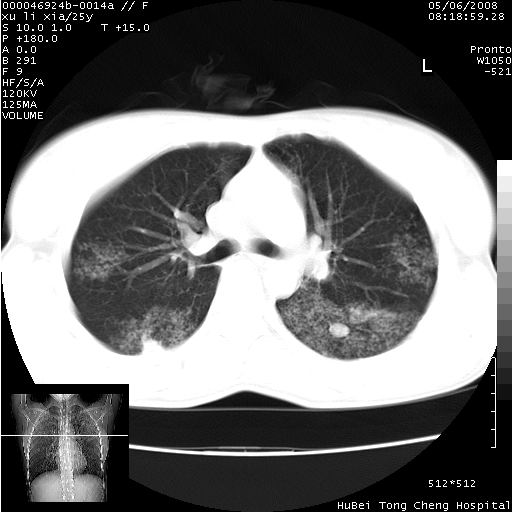

胸部ct轴位平扫(层厚10mm,螺距1.5,重建间隔10mm),图像如下:

(注:上级医院会诊胸部ct片——考虑为肺部真菌感染。)

病灶呈地图样分布于肺外围,与正常组织分界清晰+弥漫性磨玻璃影中见小叶间隔增厚呈碎石路样表现+年轻女性,无明显临床症状=肺泡蛋白沉积症?

双肺病灶以渗出影搀杂斑点状阴影为主,部分阴影融合成团片,并沿纹理明显见播散灶。支持楼主:两肺感染性病变(结核可能性大)!

双肺上叶可见节段性渗出性病变,可见树芽征像,左肺下叶背段可见结节影。